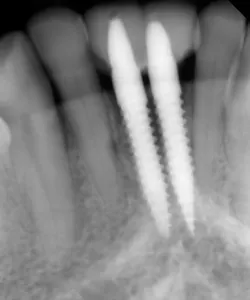

This patient presented with discomfort and mobile teeth Nos. 24 and 25. Extractions were performed, and the area was allowed to heal for six months. Mini-implants were placed in site Nos. 24 and 25 and immediately loaded with temporary crowns. The final splinted restoration was cemented two weeks later.

Figure 9: Implants restored two weeks after placement